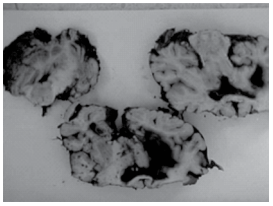

Indivíduo andando de moto sem capacete sofreu acidente de trânsito, foi arremessado em via pública, com afundamento do crânio e óbito por trauma cranioencefálico. A figura mostra cortes do encéfalo durante a necropsia.

É correto afirmar que